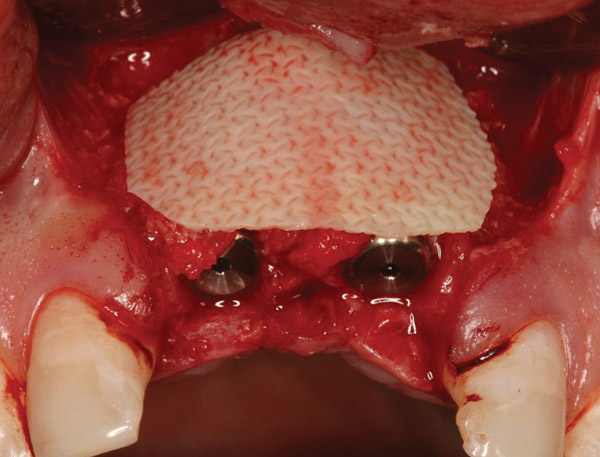

Figure 16  Freeze-dried bone allograft over a layer of autogenous bone was used to cover the dehiscences.

Figure 16

Figure 17  A bioabsorbable collagen membrane covered the grafts to promote hard-tissue regeneration.

Figure 17

Figure 20  At the second-stage surgery following a healing period of 5 months, temporary healing abutments were placed. This occlusal view shows complete regeneration of the labial plate of bone.

Figure 20